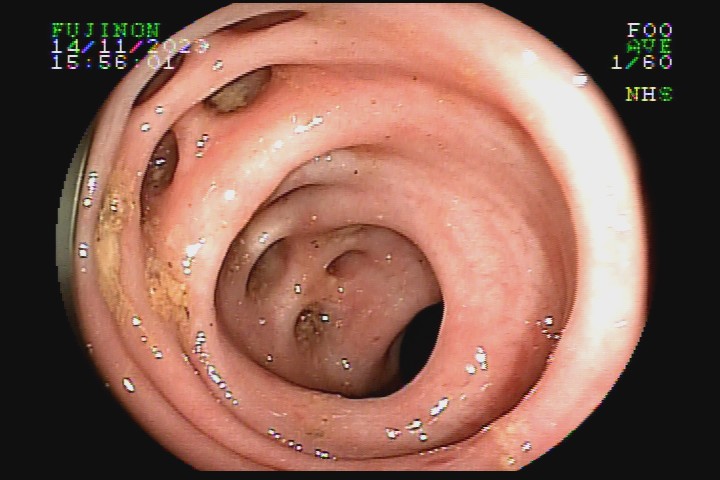

A diverticulose é uma doença adquirida, frequente entre pessoas mais idosas. Acredita-se que tenha como principal fator etiológico hábitos dietéticos relacionados com o refinamento da dieta industrializada. Pode ter uma evolução benigna por toda a vida e ser totalmente assintomática, mas pode também caracterizar-se como doença de sinais e sintomas agressivvos, com considerável morbidade e mortalidade devido às suas principais complicações: inflamação e sangramento.

A diverticulose cólica é consequência da herniação da mucosa do intestino grosso por entre as fibras musculares da parede intestinal. A diverticulose do cólon esquerdo complica mais com inflamação, e a diverticulose do cólon direito complica mais com sangramento.